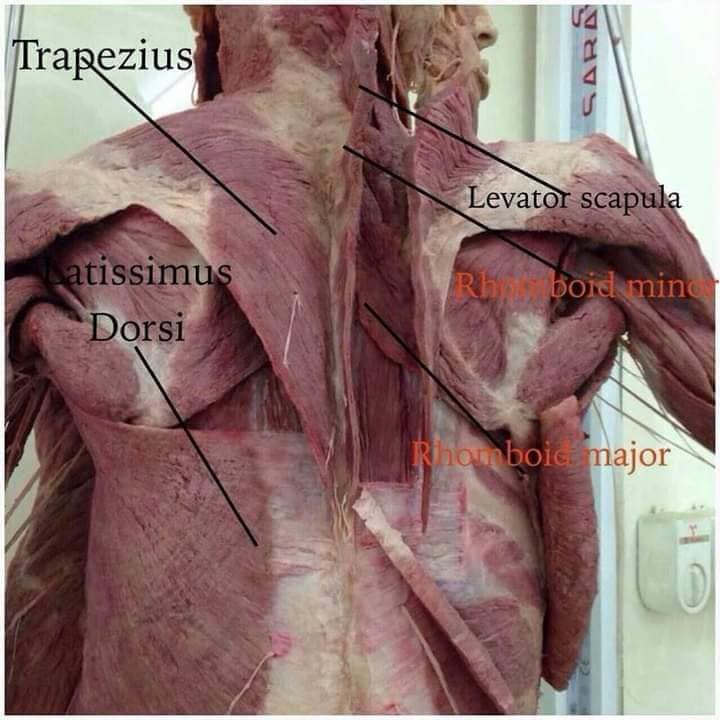

М'язова система людини є однією з основних систем організму, що відповідає за рухи, підтримання пози та стабільність. Вона складається з понад 600 м'язів, які можна класифікувати на скелетні, гладкі та серцеві м'язи. Скелетні м'язи, які є об'єктом нашого детального розгляду, дозволяють контролювати навколишній світ і виконувати різноманітні рухи. Особливу увагу в нашій статті буде приділено шейним і спинним м'язам, оскільки ці групи м'язів мають критичне значення для підтримання правильного постава та функціонування хребта.

Спинні м'язи

Спинні м'язи виконують функції підтримки хребта, а також дозволяють здійснювати рухи тулуба.

Поверхневі спинні м'язи

М'язи, що піднімають лопатку: Трапецієподібний м'яз: великий м'яз, що покриває верхню частину спини. Його функція - підтримка і рух лопаток, а також забезпечення стабільності хребта.

М'язи, що ведуть лопатку до хребта: Широкий м'яз спини: великий м'яз, що розташований в нижній частині спини. Він відповідає за рухи плечей і лопаток, а також за розширення верхньої частини тулуба.

Глибинні спинні м'язи